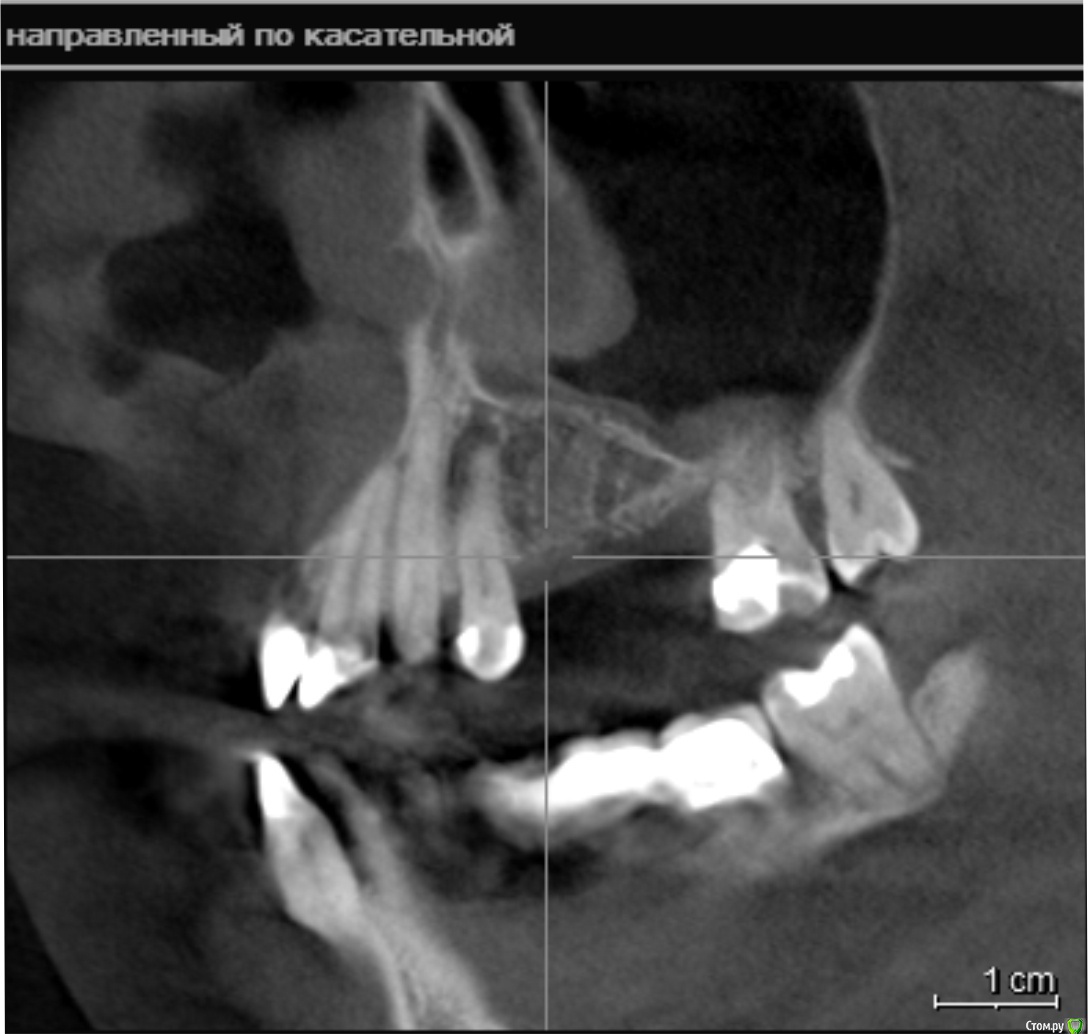

стихия Опубликовано 17 апреля, 2018 Поделиться Опубликовано 17 апреля, 2018 Здравствуйте! 8 месяцев назад были удалены верхняя левая 5-ка и 6-ка из-за кисты. Посмотрите, пожалуйста, мои снимки: возможна ли сейчас имплантация? Хватает ли там костной ткани? Проблема в том, что у меня хронический гайморит, который воспаляется каждый год, не будет ли это причиной плохой приживаемости имплантов? Можно ли при хроническом гайморите делать остеопластику? Буду очень благодарна за ответы. 2 хирурга, у которых была на очной консультации, отказались делать имплантацию в моем случае(( Ссылка на комментарий

колесников Опубликовано 17 апреля, 2018 Поделиться Опубликовано 17 апреля, 2018 (изменено) Дефект гребня в области 27 го зуба будет причиной периимплантного кармана у импланта 26. Я вижу тут 2 варианта: или Имплант Штрауман ТЛ в области 26го с синуслифтингом,+25,либо удаление 27го и мост на имплантах 25-27 Изменено 17 апреля, 2018 пользователем колесников Ссылка на комментарий

колесников Опубликовано 17 апреля, 2018 Поделиться Опубликовано 17 апреля, 2018 Импланты со своими зубами лучше не связывать. Для израильской системы слишком сложный случай,потребуется костная пластика как со стороны пазухи,так и со стороны полости рта. 27 сомнительный зуб,необходимо трезво оценить его перспективы. Если будет решение его оставить,сработает только Штрауман тл. Ссылка на комментарий